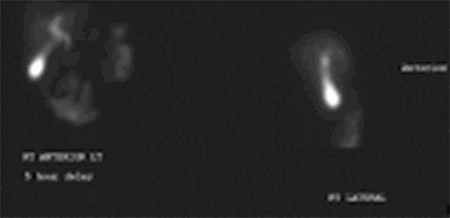

One week after her first cycle of chemotherapy, she presented to our emergency department with complaints of right upper quadrant abdominal pain. She described the pain as a sharp, stabbing in nature that was acute in onset associated with nausea and vomiting. She denies any previous episodes of similar pain. On physical exam, she was afebrile, vital signs were stable, and tenderness in the right upper quadrant was noted. Her white blood cell count was 10,000, and liver function tests revealed an elevated AST, ALT, and alkaline phosphatase. An abdominal CT scan showed marked gallbladder wall thickening without obvious cholelithiasis (Figure 1), while a HIDA scan was negative for cholecystitis with no obstruction of the cystic or common bile duct (Figure 2).

Figure 2. HIDA Scan With Filling Of Gallbladder, Patent Cystic Duct, And Common Bile Duct; No Evidence Of Acute Cholecystitis. Published with Permission